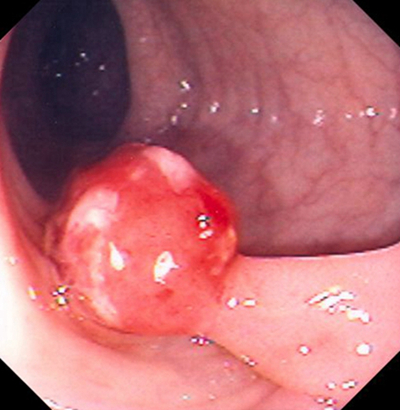

肛門癌圖片

肛癌早期症狀